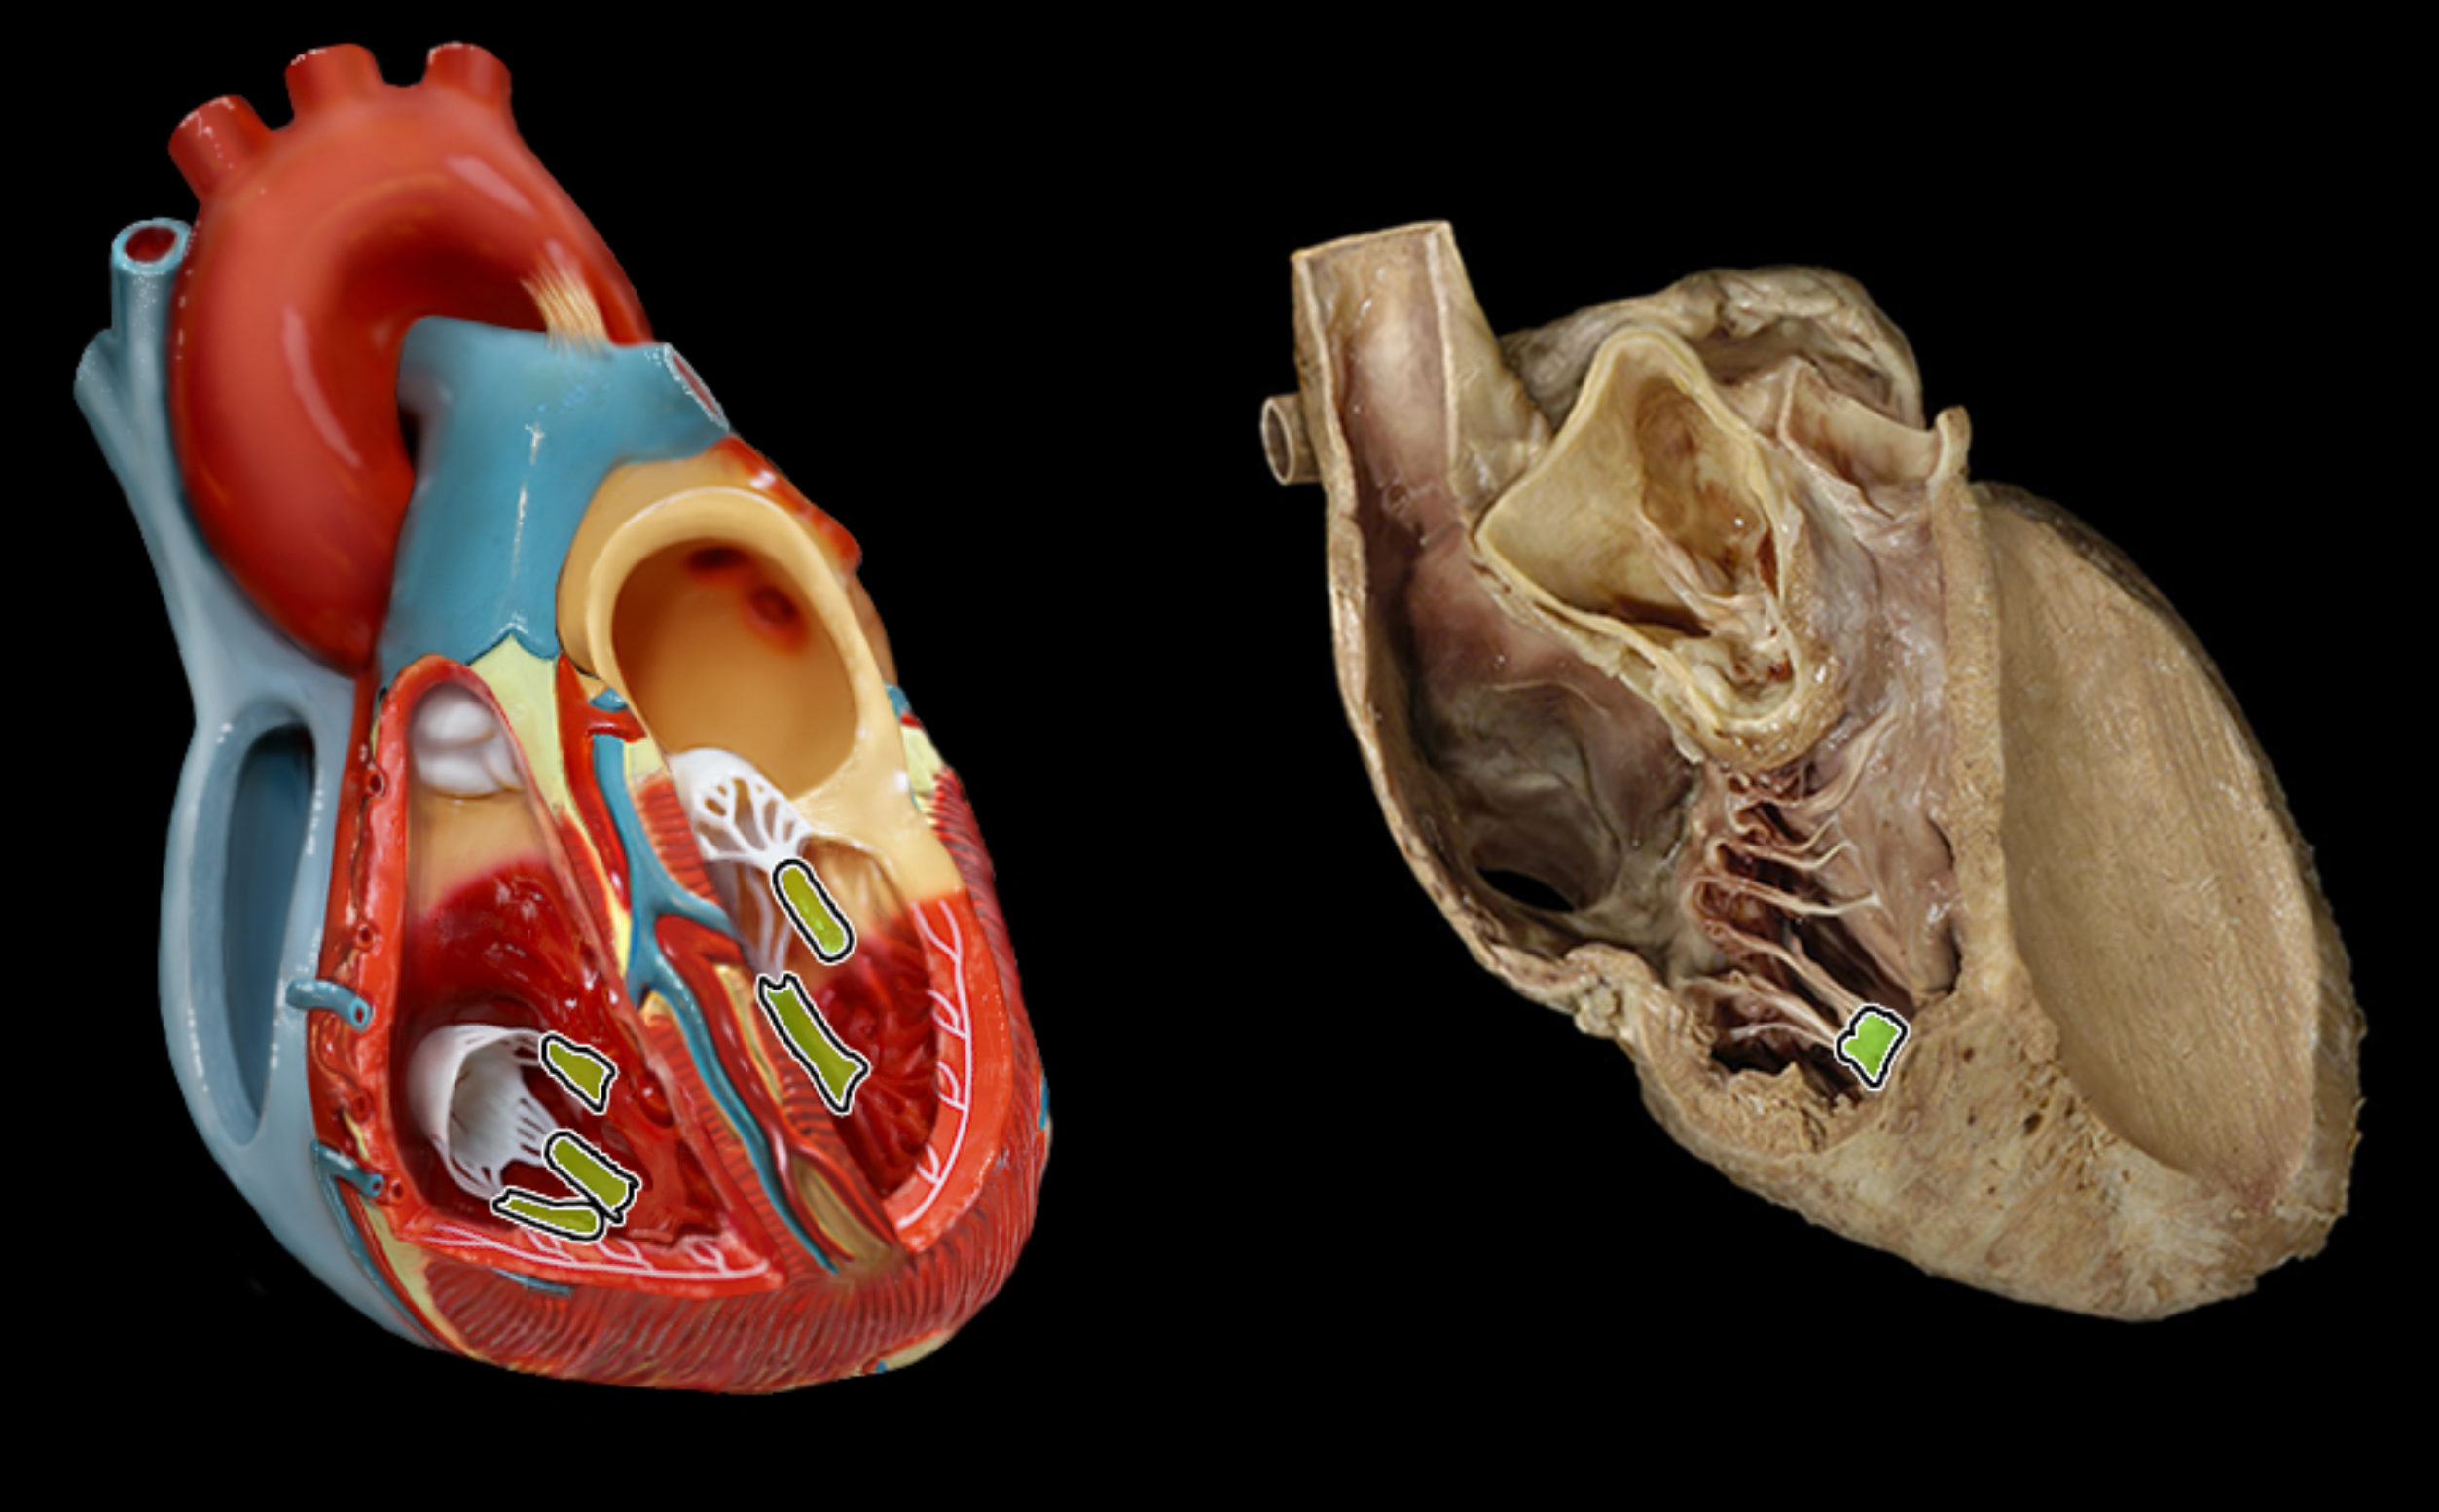

Chordae tendineae

Papillary muscle